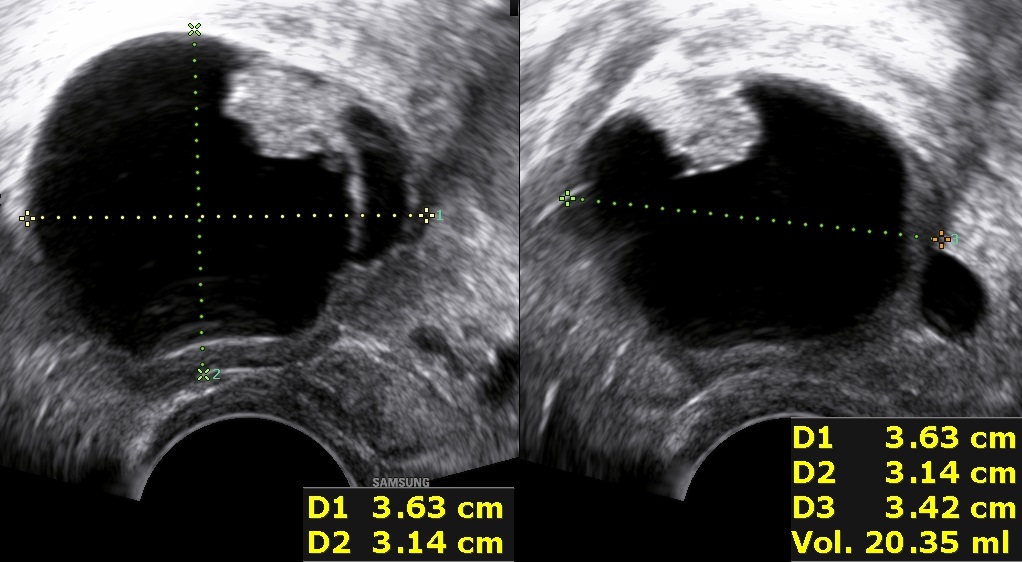

Instead, the presence of thin-walled, microcystic formations along the borders of the solid component (typically 1-3mm in size) is thought to be pathognomonic of borderline ovarian tumors (5).

Another borderline tumor with microcystic formations.